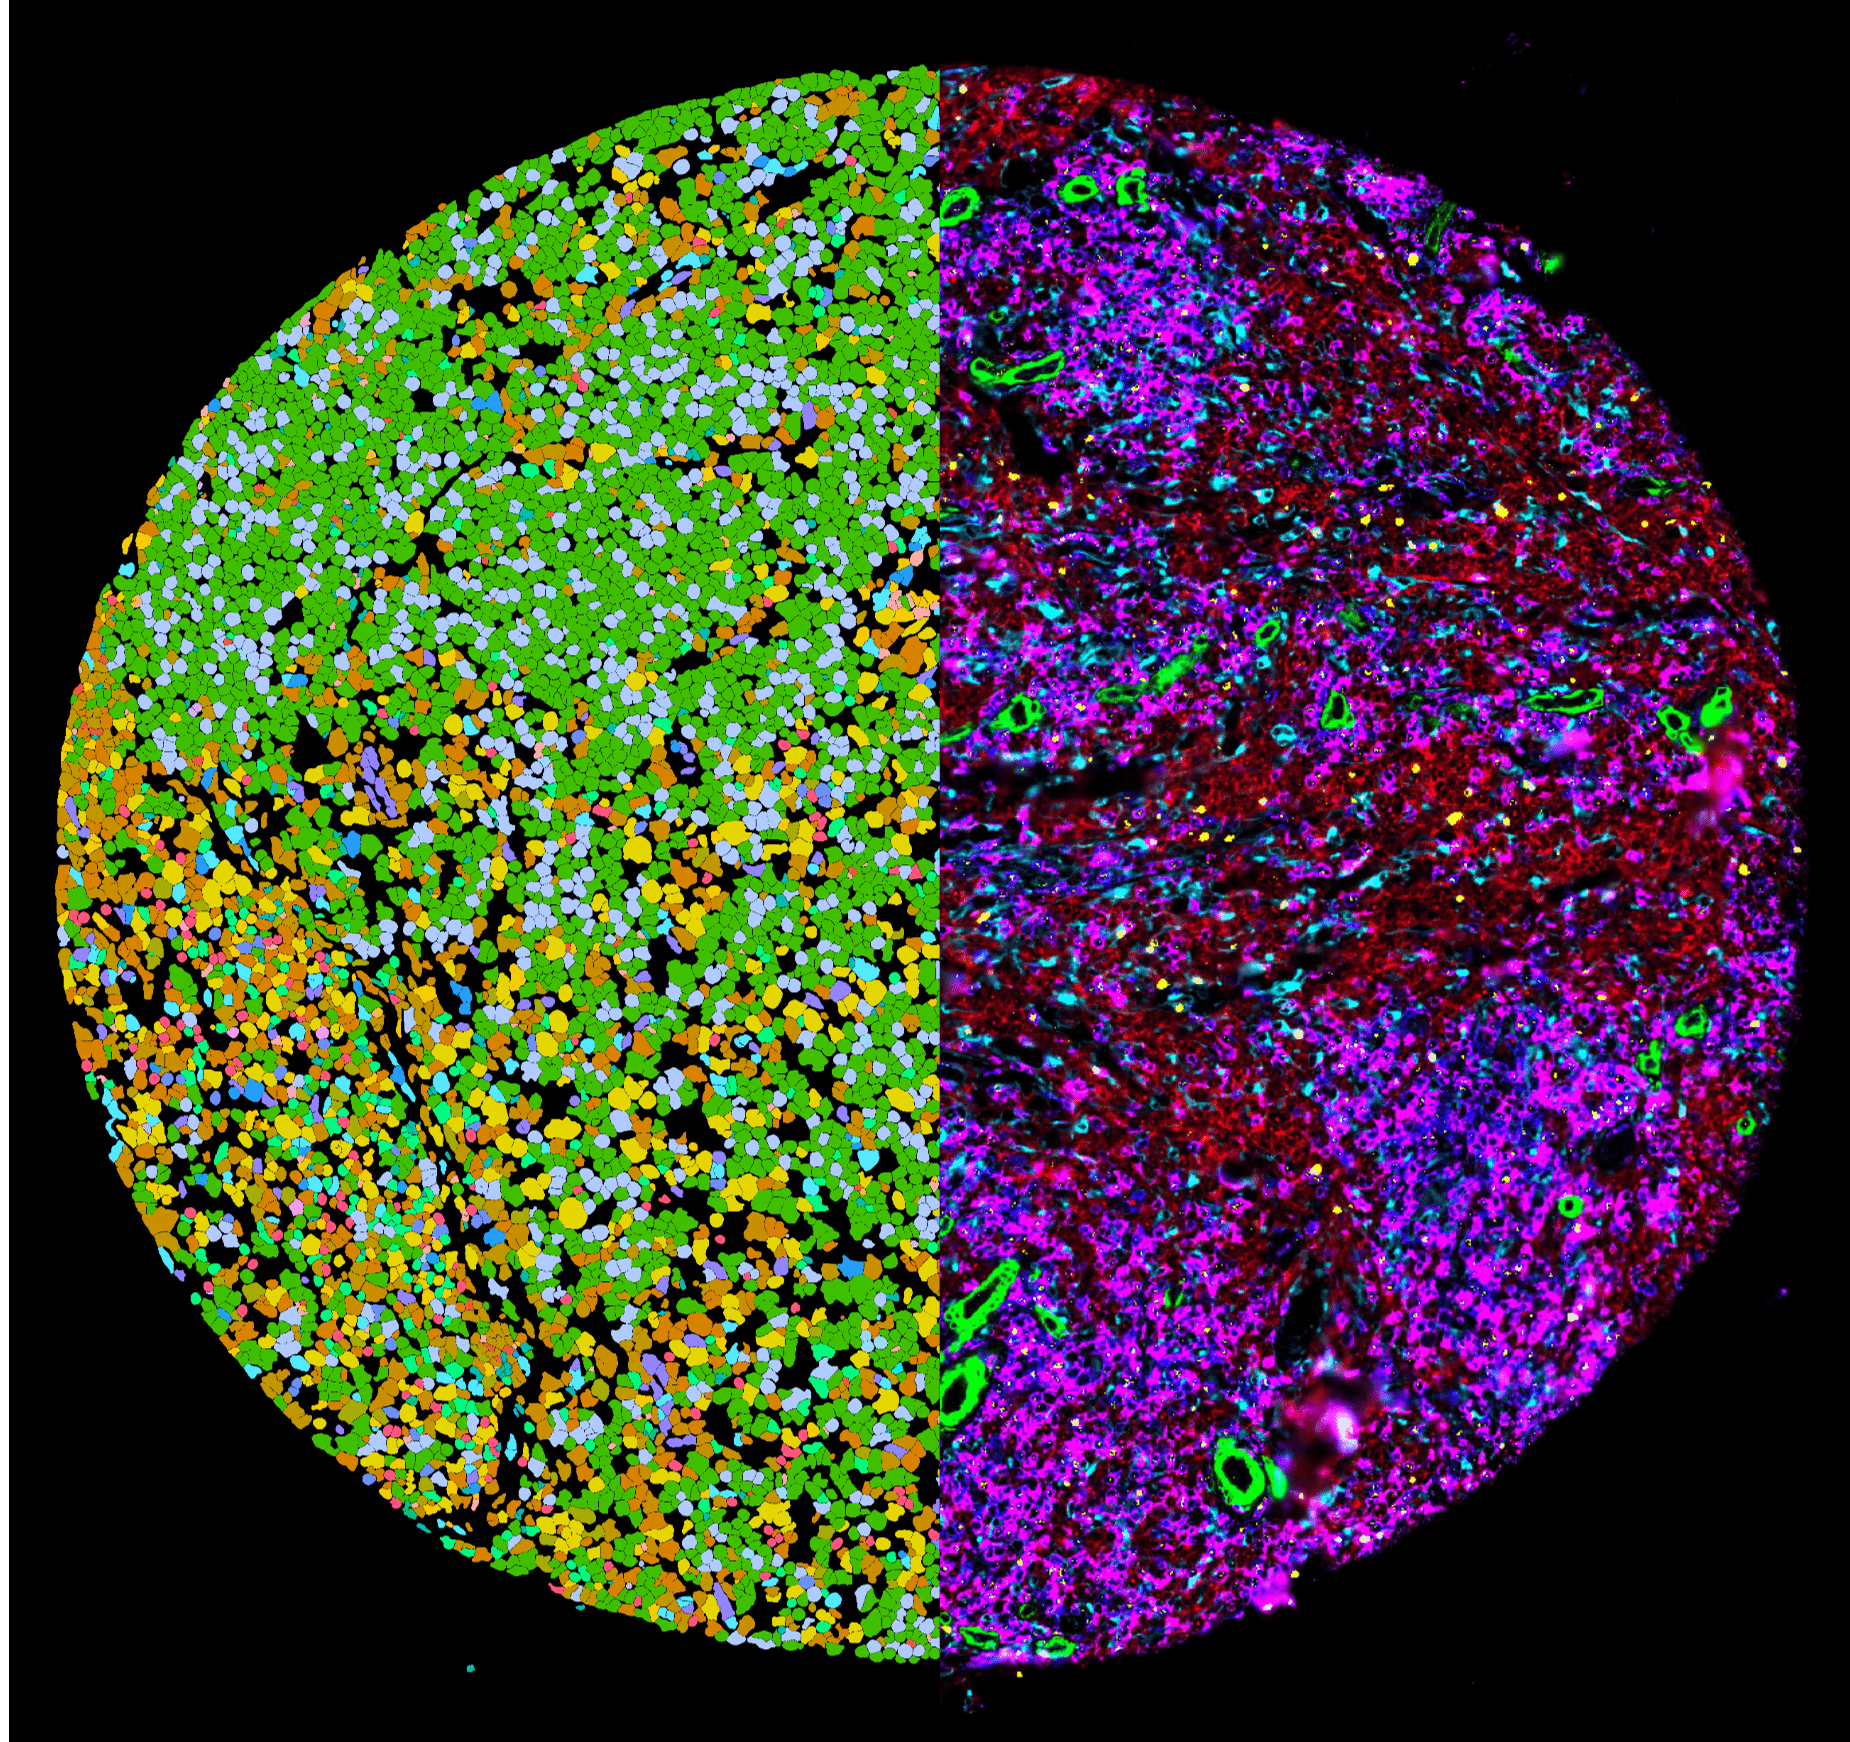

Die randomisierte, kontrollierte klinische Studie (Studienleiter: Prof. Dr. Alexandre Theocharides, MOH, USZ) untersucht, inwiefern die sogenannte Pharmakoskopie – eine am Labor von Prof. Berend Snijder (ETH Zürich) entwickelte, funktionelle Plattform für Präzisionsmedizin – zur Auswahl der individuell wirksamsten Therapie beitragen kann. Im Gegensatz zu rein genetischen Analysen analysiert die Pharmakoskopie die tatsächliche Wirkung zahlreicher Medikamente direkt an den Krebszellen der Patientinnen und Patienten – und erlaubt so eine Aussage zur zielgerichteten Behandlung.